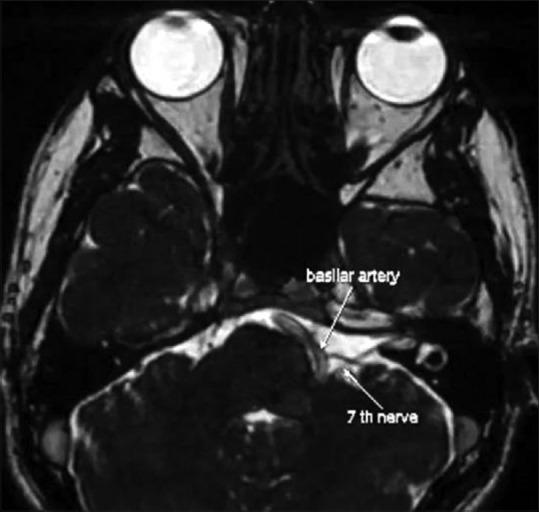

The objective of this study was to analyze the role of neuroimaging and documenting various intracranial pathologies in primary and secondary hemifacial spasm.

This retrospective study included patients with HFS who had undergone neuroimaging. The demographic profile, onset, progression, neuroimaging findings, and types of HFS were documented and analyzed.

A total of 202 patients (male = 110, female = 92) were included. The mean age of the study population was 51.81 ± 11.76 years. The right side was involved in 104 patients, the left side was involved in 97 patients and bilateral involvement was observed in one patient. Primary HFS: secondary HFS was 9.6:1. The mean age of onset of the spasms in the primary HFS group was 49.26 ± 8.35 years and in secondary HFS was 43.13 ± 12.12 years respectively. The anterior inferior cerebellar artery was the major vessel causing neurovascular conflict in primary HFS (n = 55). Facial nerve palsy was the most common cause (n = 13) of secondary HFS followed by cerebellopontine angle (CPA) tumors.

The hemifacial spasm occurs mostly in the fifth decade of life. Primary HFS is more prevalent than secondary HFS. Clinical distinction between them is difficult. Neuroimaging is essential to detect the conflicting vasculature in cases of primary HFS and pathologies like CPA tumor, cyst, and aneurysms in cases of secondary HFS.